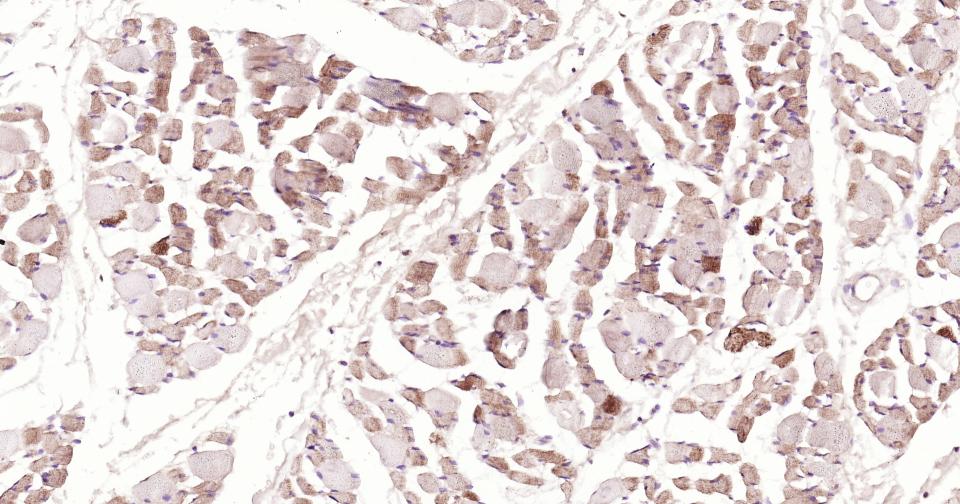

Paraformaldehyde-fixed, paraffin embedded Human Kidney; Antigen retrieval by boiling in sodium citrate buffer (pH6.0) for 15 min; Antibody incubation with AIF Monoclonal Antibody, Unconjugated(bsm-34316R) at 1:200 overnight at 4°C, followed by conjugation to the SP Kit(Rabbit, SP-0023) and DAB (C-0010) staining.

Paraformaldehyde-fixed, paraffin embedded Human Testicles; Antigen retrieval by boiling in sodium citrate buffer (pH6.0) for 15 min; Antibody incubation with AIF Monoclonal Antibody, Unconjugated(bsm-34316R) at 1:200 overnight at 4°C, followed by conjugation to the SP Kit(Rabbit, SP-0023) and DAB (C-0010) staining.

Paraformaldehyde-fixed, paraffin embedded Human Liver ; Antigen retrieval by boiling in sodium citrate buffer (pH6.0) for 15 min; Antibody incubation with AIF Monoclonal Antibody, Unconjugated(bsm-34316R) at 1:200 overnight at 4°C, followed by conjugation to the SP Kit(Rabbit, SP-0023) and DAB (C-0010) staining.

Paraformaldehyde-fixed, paraffin embedded Human Liver Cancer; Antigen retrieval by boiling in sodium citrate buffer (pH6.0) for 15 min; Antibody incubation with AIF Monoclonal Antibody, Unconjugated(bsm-34316R) at 1:200 overnight at 4°C, followed by conjugation to the SP Kit(Rabbit, SP-0023) and DAB (C-0010) staining.

Paraformaldehyde-fixed, paraffin embedded Human Cerebellum; Antigen retrieval by boiling in sodium citrate buffer (pH6.0) for 15 min; Antibody incubation with AIF Monoclonal Antibody, Unconjugated(bsm-34316R) at 1:200 overnight at 4°C, followed by conjugation to the SP Kit(Rabbit, SP-0023) and DAB (C-0010) staining.

Paraformaldehyde-fixed, paraffin embedded Human Skeletal muscle; Antigen retrieval by boiling in sodium citrate buffer (pH6.0) for 15 min; Antibody incubation with AIF Monoclonal Antibody, Unconjugated(bsm-34316R) at 1:200 overnight at 4°C, followed by conjugation to the SP Kit(Rabbit, SP-0023) and DAB (C-0010) staining.

Paraformaldehyde-fixed, paraffin embedded Human Colon Cancer; Antigen retrieval by boiling in sodium citrate buffer (pH6.0) for 15 min; Antibody incubation with AIF Monoclonal Antibody, Unconjugated(bsm-34316R) at 1:200 overnight at 4°C, followed by conjugation to the SP Kit(Rabbit, SP-0023) and DAB (C-0010) staining.